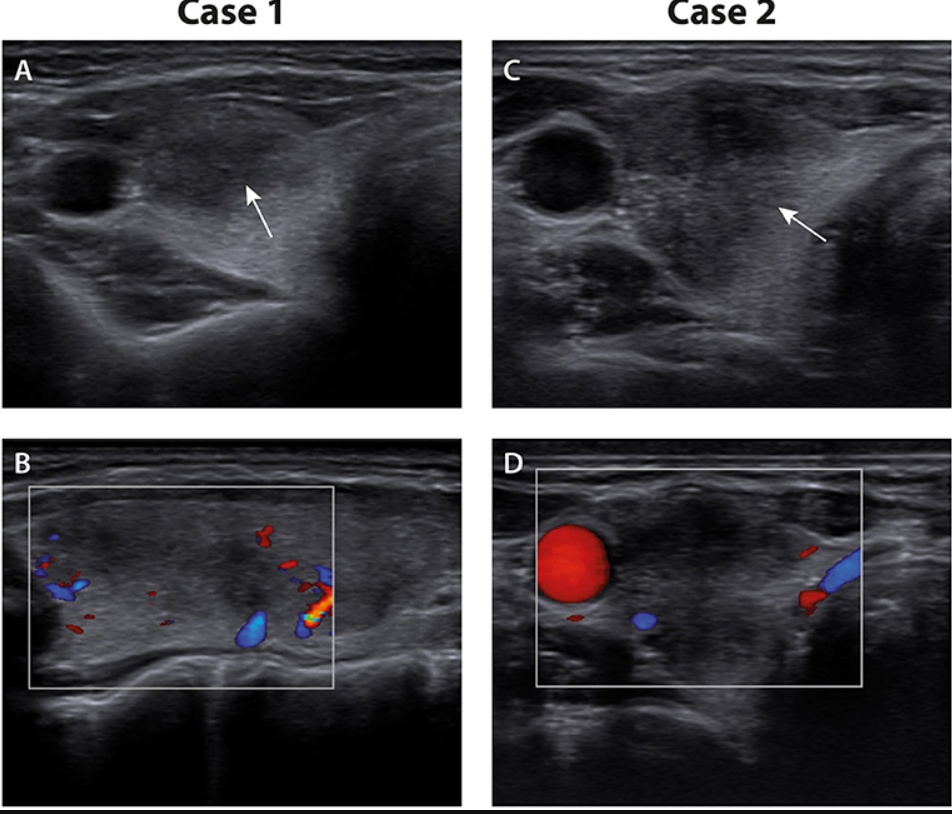

Autre exemple, autre organe: une femme 49ans déclenche une thyroidite dans les 2 semaines après sa dose de Moderna. Une aspiration d’un nodule thyroidien donne des lymphocytes, des marcophages et des cellules géantes multinucléées …

Case Report: Two Cases of Subacute Thyroiditis Following SARS-CoV-2 VaccinationSubacute thyroiditis is an inflammatory thyroid disorder associated with viral infections. Rare cases of subacute thyroiditis have also been described following vaccination. Recently, a few cases of s…https://www.frontiersin.org/articles/10.3389/fmed.2021.737142/full